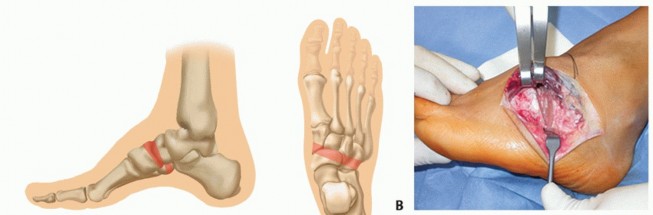

### Case 2

A 32-year-old man with severe equinocavovarus had his major problems combined forefoot and hindfoot equinus, hindfoot varus, a cavus component, and clawing of the toes.

After Achilles tendon lengthening, a split PTT transfer, a Steindler procedure, a Chopart fusion, a dorsiflexion first metatarsal osteotomy, and a modified Jones procedure, a plantigrade functional foot was restored.

FIG 7A,B shows preoperative findings and FIG 7C,D shows findings 1 year postoperatively.

* **FIG 7 • Preoperative (A,B) and postoperative (C,D) clinical and radiographic findings of a 32-year-old patient with severe equinocavovarus foot deformity bilaterally.**